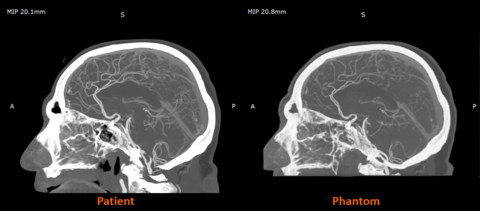

RadioMatrix is the first and only 3D printing material that enables precise control of radiopacity - allowing users to produce patient-specific models with repeatable, consistent, and fully tunable visibility on X-ray based imaging. Stratasys developed RadioMatrix to support a new era of medical imaging. Its unmatched fidelity for computed tomography (CT) phantoms was later underscored by research conducted with Siemens Healthineers, which validated RadioMatrix’s capabilities and accuracy for accelerating innovation in device testing, calibration, and education.

Early research from the Stratasys–Siemens Healthineers collaboration shows that 3D printed RadioMatrix™ phantoms can closely replicate real human tissue in CT imaging, with deviations reported as low as single Hounsfield units (HU) in critical areas such as grey matter and veins. By combining Stratasys’ Digital Anatomy™ 3D printing technology and radiopaque materials with advanced imaging algorithms, the partners are demonstrating anatomically realistic, radio-accurate phantoms that preserve fine anatomical details and pathological variations while offering a more consistent, ethical alternative to cadavers. These models are expected to improve how radiologists validate and optimize CT protocols and accelerate the development of new imaging algorithms for more precise diagnosis and treatment planning.